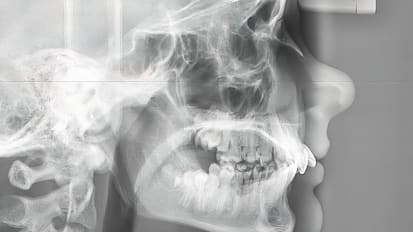

Improving Patient Care, From General Dentistry to the Most Complex Craniofacial Reconstructions

Robin Yang leads the Johns Hopkins Division of Oral and Maxillofacial Surgery and Dentistry through growth and change.